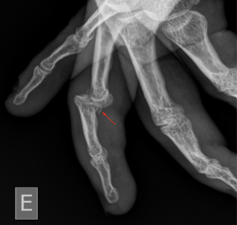

Image 2: Magnification of the X-ray above demonstrates an avulsion fracture of the base of the phalanx, indicating a volar plate avulsion fracture. Case courtesy of Leonardo Lustosa, Radiopaedia.org, rID: 99559

Volar plate injuries, including avulsion or oblique fractures into the PIP joint, are commonly seen with dorsal PIP dislocations. This injury warrants careful consideration in any patient with a history of a hyperextension mechanism injury to any digit. This will often be reported as having a “jammed” finger when playing contact sports or attempting to catch/corral a ball.3 Volar plate fractures involving greater than 30% of the articular surface may no longer be stable and may require surgical fixation. These warrant timely follow-up with hand surgery.3,4 If left untreated, dorsal dislocations and volar plate injuries can result in a persistent swan neck deformity. Irreducible dorsal dislocations, while rare, should prompt concern for an interposed volar plate. These require prompt orthopedic consultation for open reduction.5 Central slip extensor tendon injuries can be seen with volar PIP dislocations and can result in a Boutonniere deformity if missed or left untreated.4

- X-rays, with multiple views, are important to assess for associated fractures with any dislocation injury.